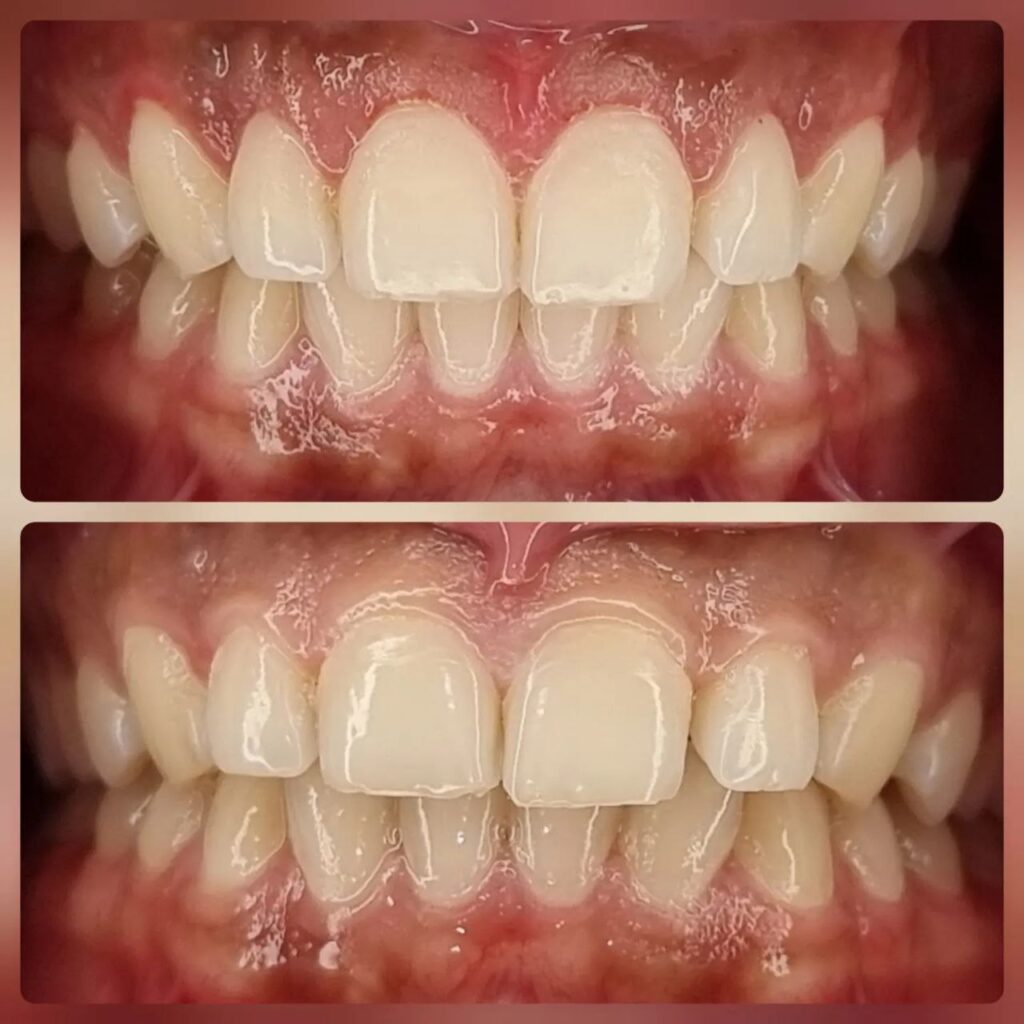

ارتودنسی دندان

از ارتودنسی به عنوان یکی از خدمات دندانپزشکی زیبایی، برای درمان انواع مشکلات دندانی و فکی استفاده میشود. این روش برای کودکان و هم برای بزرگسالان مناسب است. ارتودنسی میتواند فواصل بین دندانها را به خوبی رفع کرده و باعث ترتیب و هماهنگی دندانها شود.

امروزه، ارتودنسی نامرئی نیز مورد استفاده قرار میگیرد که این روش بدون سیمهای قابل مشاهده، انجام میشود؛ بنابراین افرادی که نمیخواهند سیمهای ارتودنسیشان نمایان شود، میتوانند از این روش استفاده کنند.